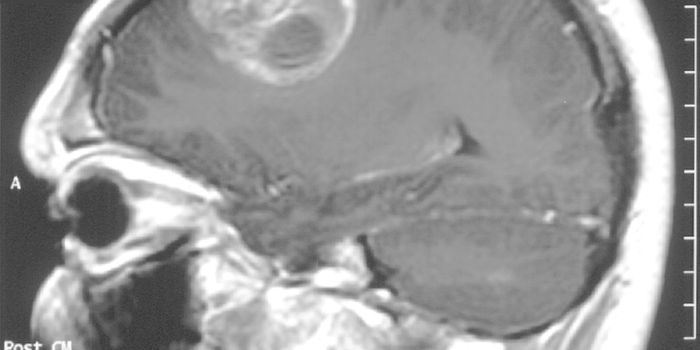

MAR 08, 2018ImmunologyOne of the most lethal forms of brain cancer owes most of its deadliness to its evasion of the immune system - a nasty t ...

FEB 09, 2025CancerGlioblastoma (GBM), an aggressive form of cancer that grows in the brain or spinal cord, occurs at an incidence rate of ...

JUN 29, 2023NeuroscienceGlioblastoma is a type of rare brain cancer that originates in the brain or spinal cord. Glioblastoma can occur at ...

APR 18, 2017ImmunologyA rare and lethal brain tumor more often than not leads to death not much longer than one year after diagnosis, even wit ...